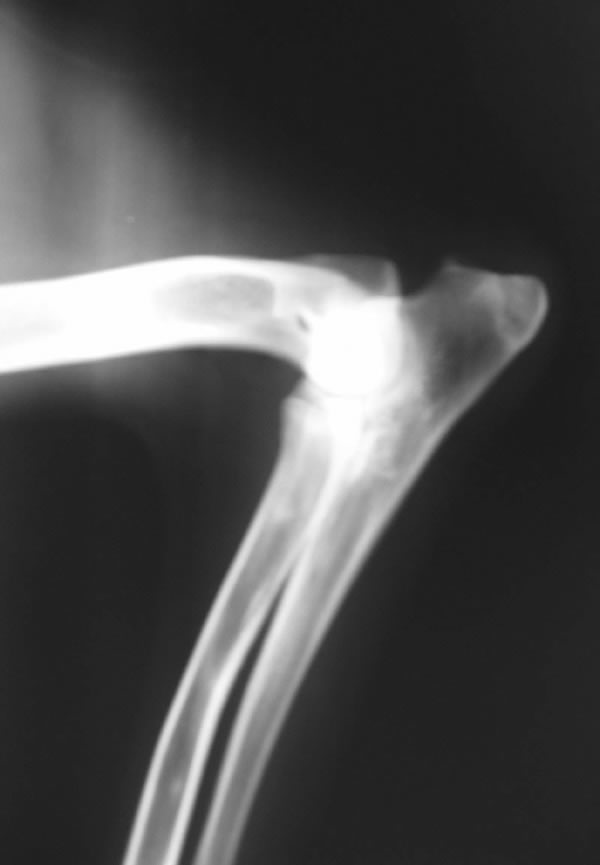

Eddy is a beautiful son of Anouc-Lar Leomegy (Nuky) and Agala Zomboch daughter of top producing stud 6XWUSV 5XFCI Emir Chabet, born December 25, 2003. He is line bred to 2XBSP Troll vom Körbelbach. He is a huge male with a very good temperament. He is good with kids and very tolerant with other animals. He likes bite work, tracking and watching Animal Planet. His obedience on field an off field is coming along very nicely. We took Eddy for his OVC certification and the veterinarian said Eddy has the best hips she's seen in five years on a GSD.

Eddy's X-Rays